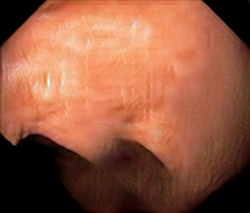

A few sample images and the corresponding masks of the polyp dataset in HyperKvasir are shown in Fig 2. The polyp images are RGB images. The masks of the polyp images are single-channel images with white () for true pixels, which represent polyp regions, and black () for false pixels, which represent clean colon or background regions. In this dataset, there are different sizes of polyps. The distribution of polyp sizes as a percentage of the full image size is presented in the histogram plot in Fig 3, and we can observe that there are more relatively small polyps compared to larger polyps. Additionally, a subset of this dataset was used to prove that the performance of segmentation models trained with small datasets can be improved using our SinGAN-Seg pipeline, and the whole dataset was used to show the effect of using SinGAN-Seg generated synthetic images instead of a large dataset which has enough data to train segmentation models. In this regard, this dataset was used for two purposes:

After training SinGAN-Seg models, we generated random samples per real image using the input scale , which is the lowest scale that uses a random noise input instead of a re-scaled input image. For more details about these scaling numbers and corresponding output behaviors, please refer to the vanilla SinGAN paper [56]. Three randomly selected training images and the corresponding first synthetic images generated using scale are depicted in Fig 4. The first column of the figure represents the real images and the ground truth mask annotated from experts. The rest of the columns represent randomly generated synthetic images and the corresponding generated mask.

In Fig 7, we provide a visual comparison between pure generated synthetic images and style transferred images ( = ). Samples with the style transfer ratio are not depicted here because it is difficult to see the differences visually. The first column of Fig 7 shows the real images used as content images to transfer styles. The rest of the images in the first row of each image shows synthetic images generated from SinGAN-Seg before applying the style transferring algorithm. Then, the images in the second row in the figure show the style transferred synthetic images. Differences of the synthetic images before and after applying the style transfer method can be easily recognized from images of the second reference image (using and rows in Fig 7).